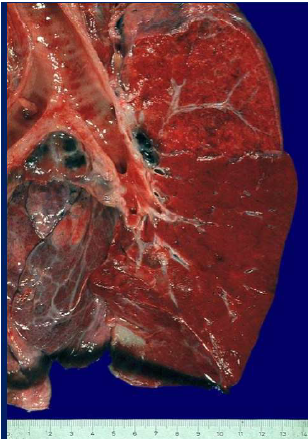

Polmone più o meno normale, forma tronco-conica a base maggiore inferiore (base),

chiaramente una sola scissura, lateralità rapporto tra le strutture vascolari e i bronchi, macchie per

problemi di fissazione, piccoli noduli antracotici (normale in un polmone di una persona che vive in

città